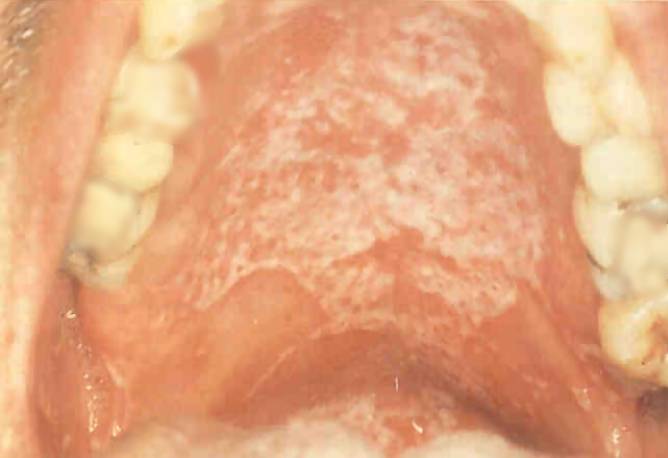

Oral thrush

The patients’ palate (top) and tongue (bottom) show the symptoms of oral thrush, an opportunistic fungal infection.

As the immune system is weakened further, serious symptoms may appear. For example: Skin rashes, fever, fatigue, night sweats, oral thrush, etc .This stage is often called “symptomatic HIV infection”. However, such relatively light symptoms will finally be followed by severe health problems. This final stage of the infection is usually referred to as “full-blown AIDS”. The immune system has broken down, and, as a result, any number of illnesses now manifest themselves. For example: Pneumocistis (PCP), an especially dangerous form of pneumonia, tuberculosis, Kaposi’s sarcoma (KS), an otherwise rare form of skin cancer, and various other cancers, “wasting”, i.e. continuing weight loss, various brain diseases, and many more, eventually killing the patient.